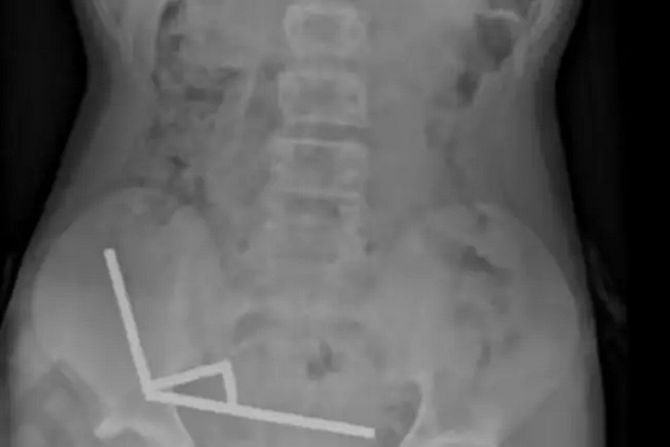

Lekari su ustanovili da su se magneti spojili i formirali četiri lanca unutar njegovih creva. Hirurzi su potom izvadili magnete i uklonili delove dečakovih oštećenih creva.

Kako su naveli lekari, dečak je progutao između 80 i 100 neodimskih magneta velike snage veličine 5x2 milimetara, sedam dana pre hospitalizacije,